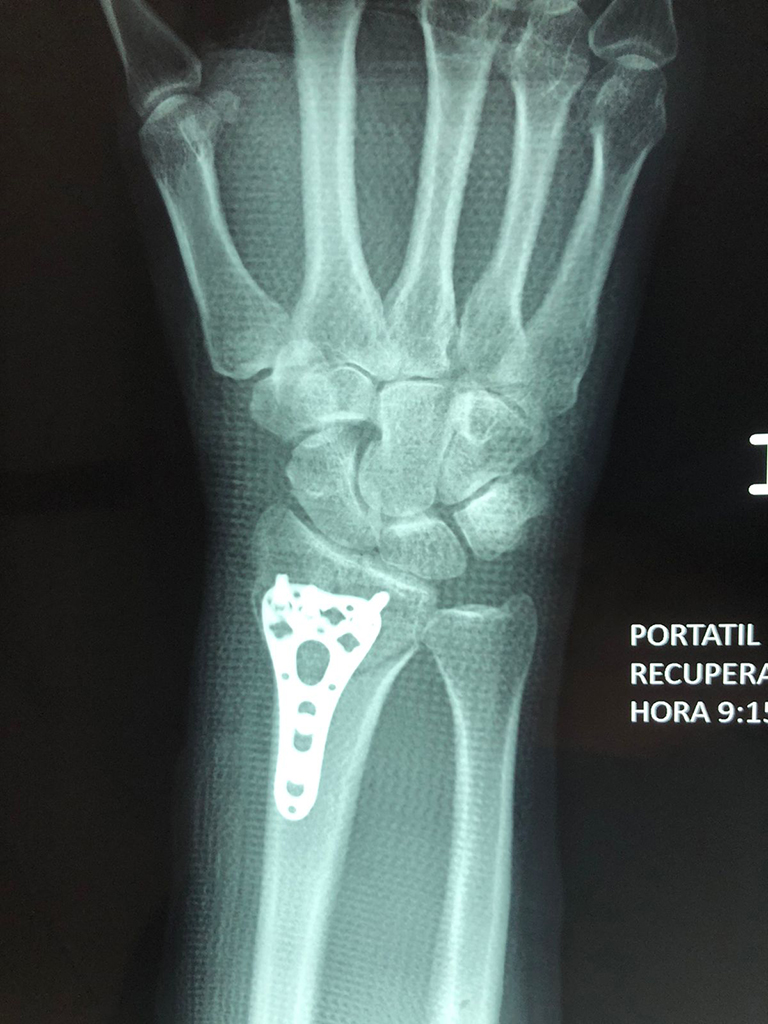

Cirugías de Calcaneo - Cirugías de Muñecas y Manos

Los procedimientos más comunes en cirugía de la mano son aquellos destinados a reparar traumatismos, incluyendo lesiones de tendones, nervios, vasos sanguíneos, y articulaciones; huesos fracturados; y quemaduras, cortes, y otros daños de la piel.